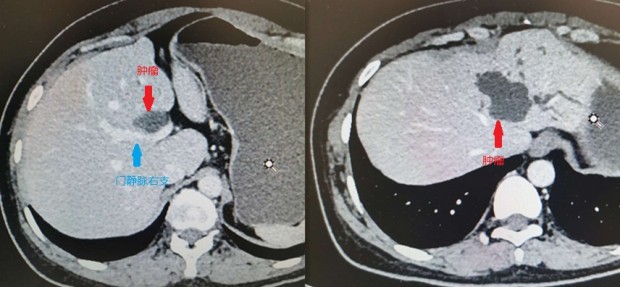

抗击疫情众志成城 精湛手术保驾护航